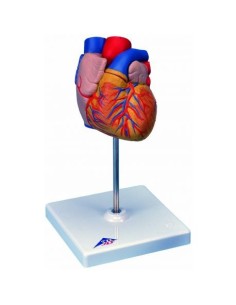

Du crâne en 22 parties à verrouillage magnétique aux modèles de colonne vertébrale, des modèles d'articulation aux modèles de cœur, chaque pièce de notre collection est conçue pour une immersion totale dans l'étude de l'anatomie humaine. Nos modèles, réalisés à partir de scans d'os réels, garantissent une expérience tactile authentique et une fidélité de poids presque identique aux originaux.